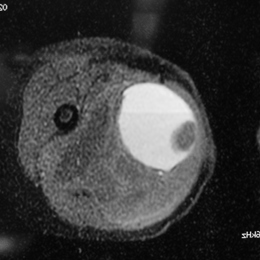

Radiographic imaging is used to help form a diagnosis. These include X-Ray, MRI, CT and Bone Scans

An example of an MRI is shown.